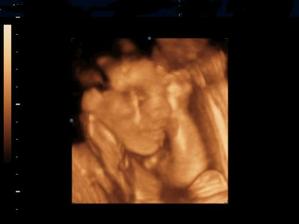

Naše kinderka

Dňa 24.8.2009 o 9.15 sa nám sekciou narodili naše krásne dvojičky Vanesska 2280 g a Larinka 2990 g. Robia nám veľkú radosť a moc ich ľúbime...